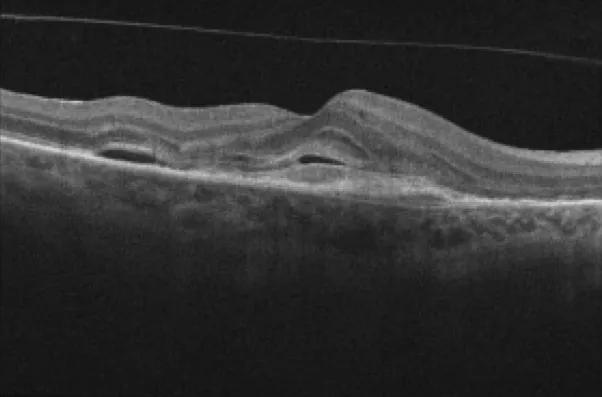

Optical coherence tomography image showing macular fluid

Despite having nAMD that was refractory to other treatment, most patients in the study showed reduction in macular fluid as seen on optical coherence tomography: